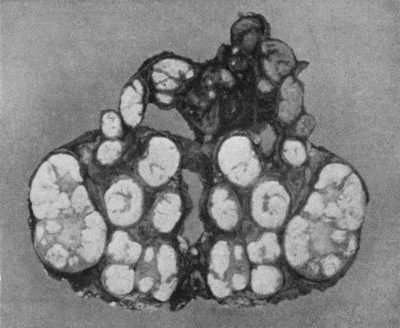

59.Dermoid Cyst of Ovary 213